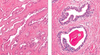

Describe the corpus luteum?

Stromal, granulosa and thecal cells invade cavity to differentitate into luteal cells

Contain lipid and become vascularised

What is the function of the corpus luteum?

Produces progesterone and oestrogen to prepare endometrium for implantation

How long does the corpus luteum last for?

14 days without fertilisation

No fertilisation > regresses to form corpus albicans